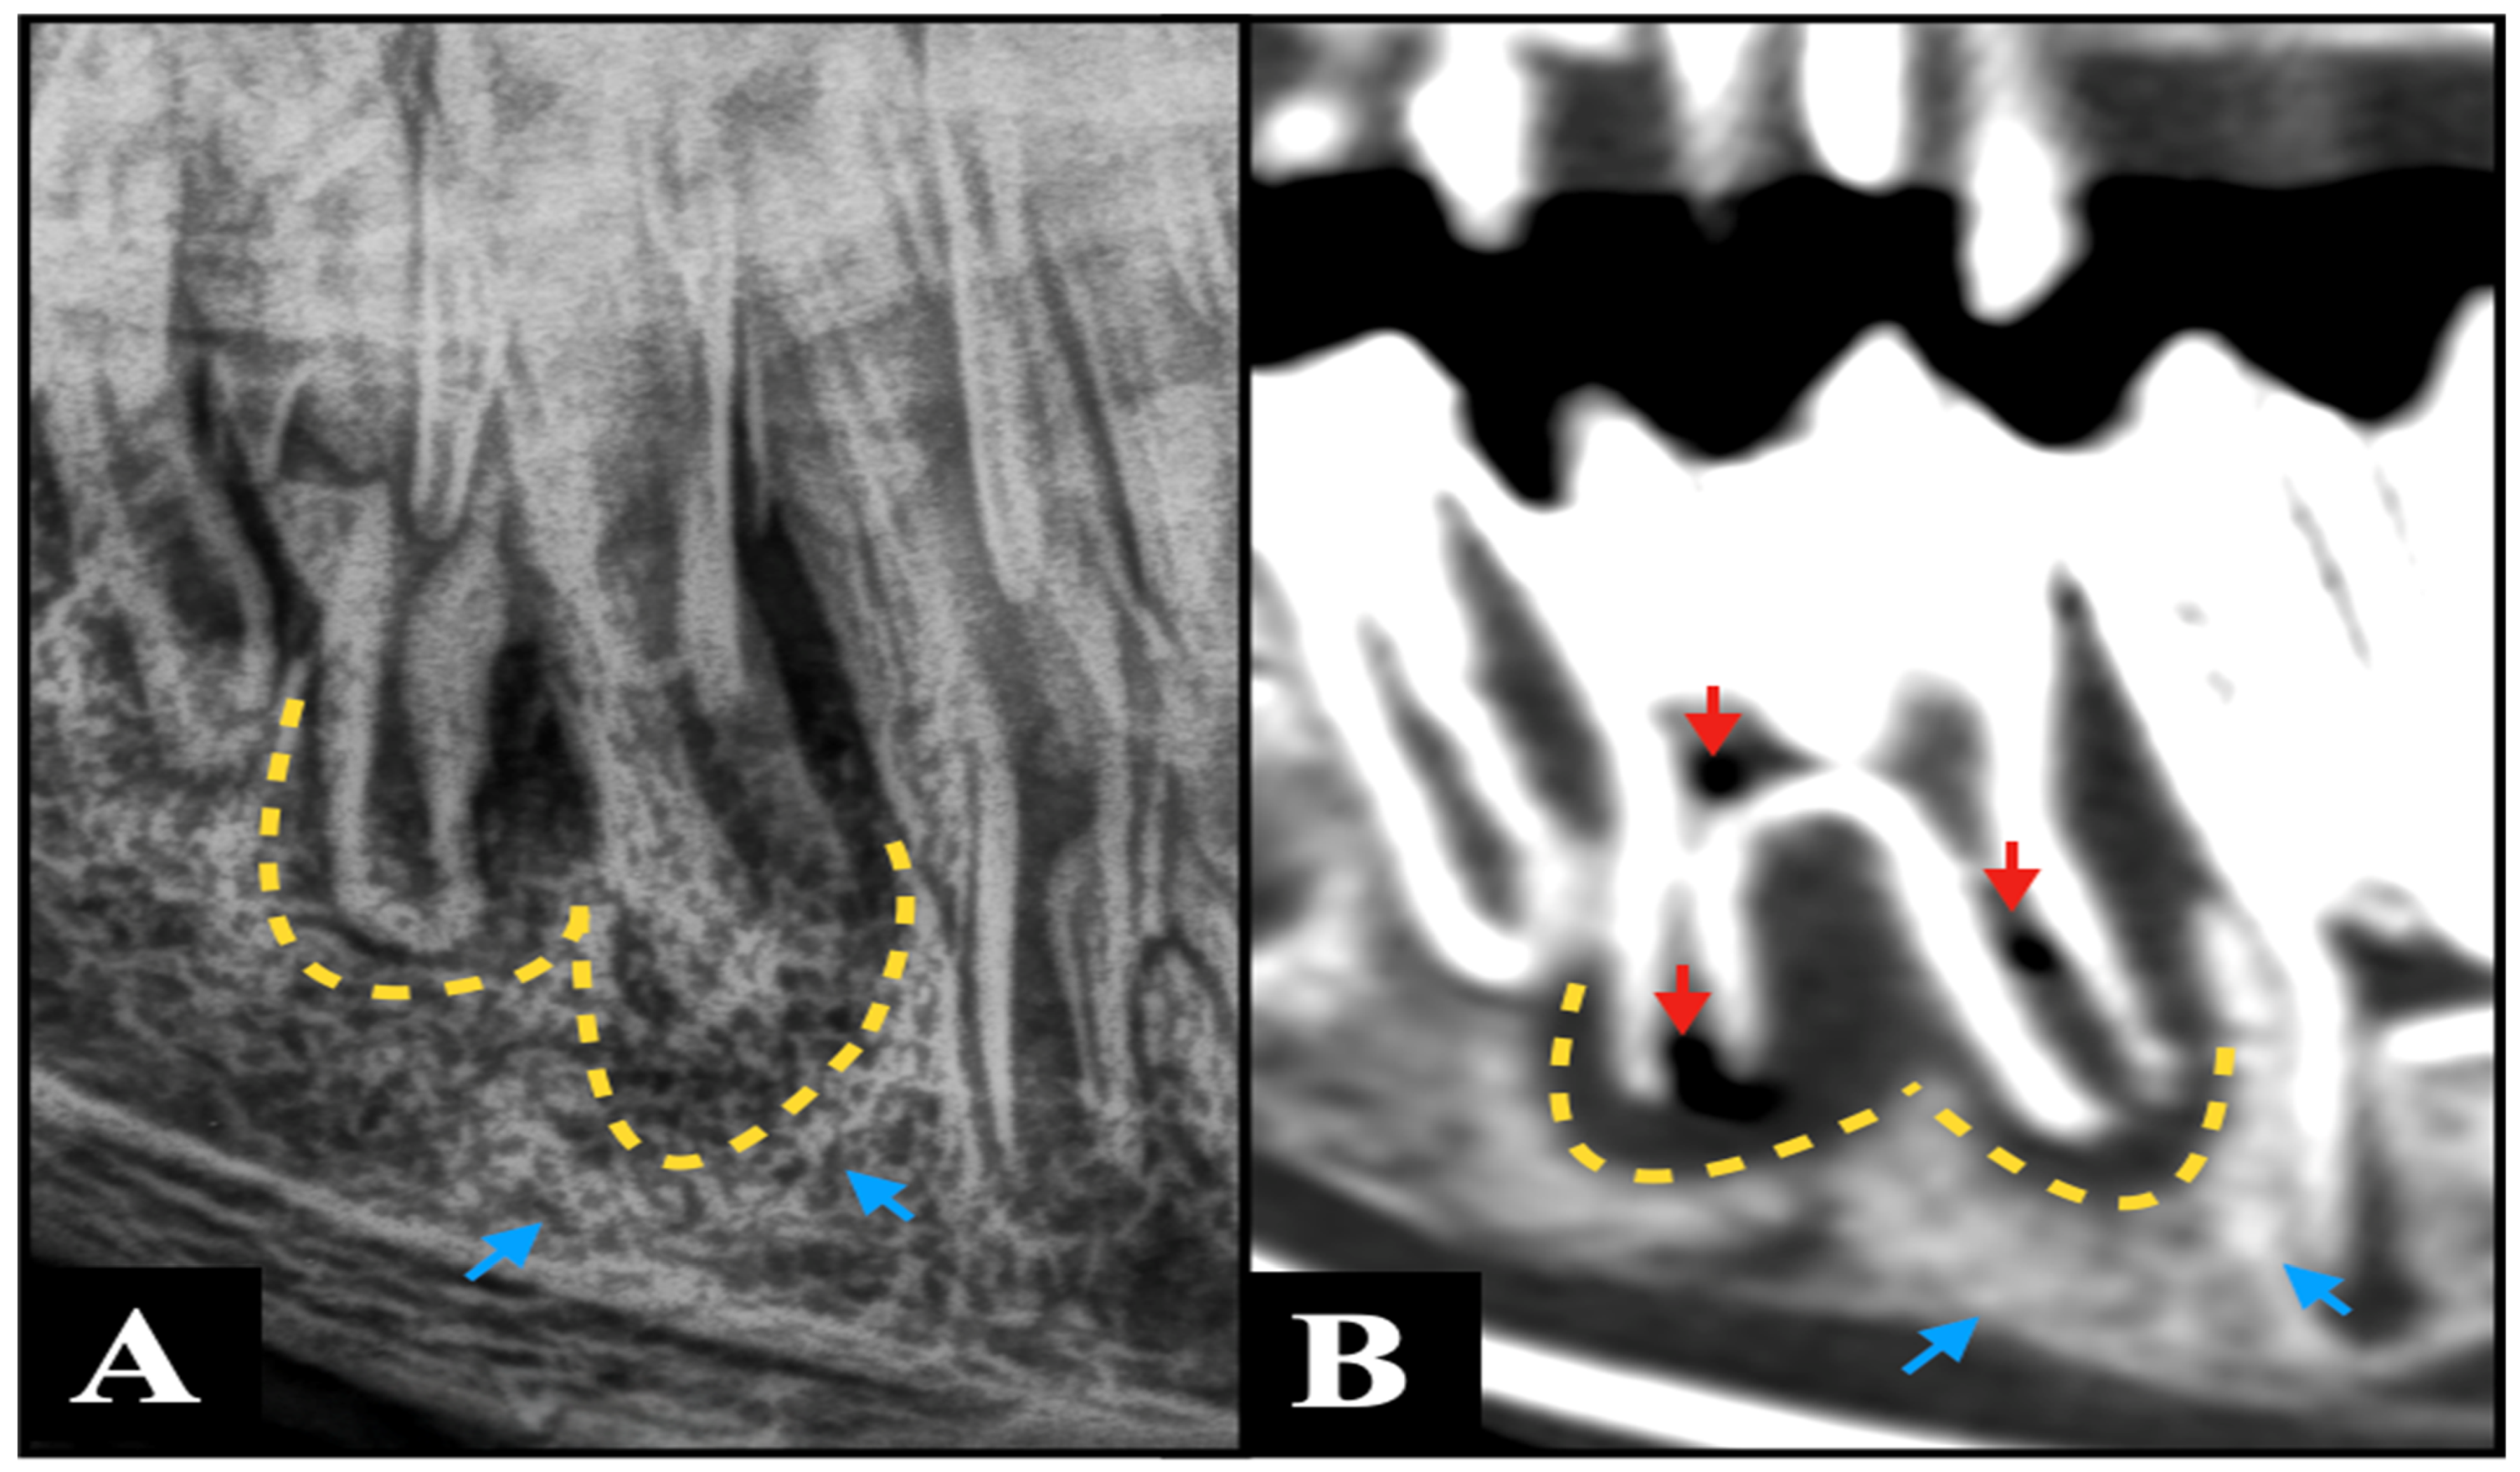

The lack of superimposition of multiple anatomical structures provided by CT is most likely the reason why widening of the periodontal ligament space, clinical crown fractures, radicular and pulpar changes, and the presence of cementomas and hypercementosis were detected more frequently by CT than by radiography in this study. Specifically, the marked over-representation of pulpar changes detected by CT compared to radiography (Figure 2) is similar to what was previously found in horses [22]. Pulpar changes included in this study were mostly represented by pulp stones, whose size makes them undetectable on radiographs. Furthermore, the possibility of performing multiplanar reconstruction is most likely responsible for the easier detection of sequestration, periosteal reaction, mandibular expansion, and cortical destruction on CT images compared to radiography. These multiplanar views allow for more precise localization and characterization of pathology, enhancing diagnostic confidence (Figure 3).

Figure 2.

An R45°V-LDO oblique radiograph (A) and a bone window sagittal plane computed tomography multiplanar reconstruction image (B) demonstrate concordant findings consistent with periapical infection of Triadan 309, characterized by marked widening of the periodontal ligament space (yellow dotted arrow) and sclerosis of the neighboring alveolar bone (blue arrows). However, CT additionally revealed multiple gas foci within the pulp system of this tooth (red arrows)—a finding that was not detectable on the radiographic projection.